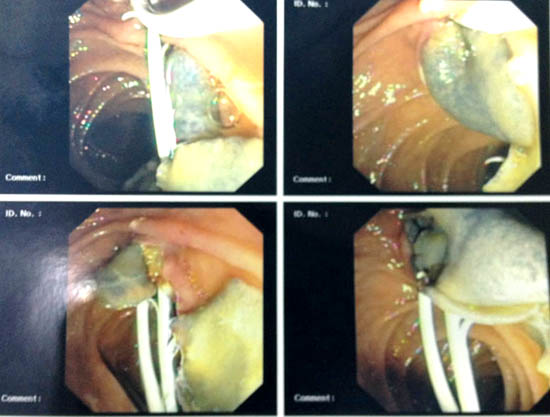

Chụp đường mật (Cholangiography)

Nội soi mật tụy ngược dòng (ERCP) được xem là kỹ thuật chuẩn vàng trong chẩn đoán hình ảnh ở đường mật trên các bệnh nhân nhiễm trùng mạn tính. Nó cũng hỗ trợ trong quản lý ca bệnh sán lá gan lớn, cần phải cắt cơ vòng dưới hướng dẫn của ERCP và loại bỏ sán trưởng thành kẹt do nhiễm trùng mạn tính và gây tắc đường mật.

Hút dịch túi mật dưới hướng dẫn siêu âm (US-guided gallbladder aspiration)

Thủ thuật này thường giúp phát hiện hoặc nghiên cứu tìm trứng sán trong túi mật, thậm chí trên nhiều ca xét nghiệm phân âm tính.